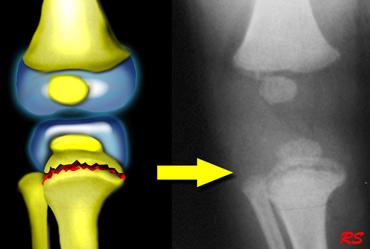

Gãy xương kiểu tay xách xô (Bucket handle fractures)

Gãy xương kiểu tay xách xô về bản chất giống với gãy xương góc.

Mảnh xương bị bong ra có kích thước lớn hơn và được nhìn thấy theo hướng “en face” (nhìn thẳng) như hình đĩa hoặc tay xách xô.

Hình ảnh

Gãy xương kiểu tay xách xô ở đầu trên xương chày. Mảnh gãy hành xương được nhìn thấy như hình đĩa hoặc tay xách xô.